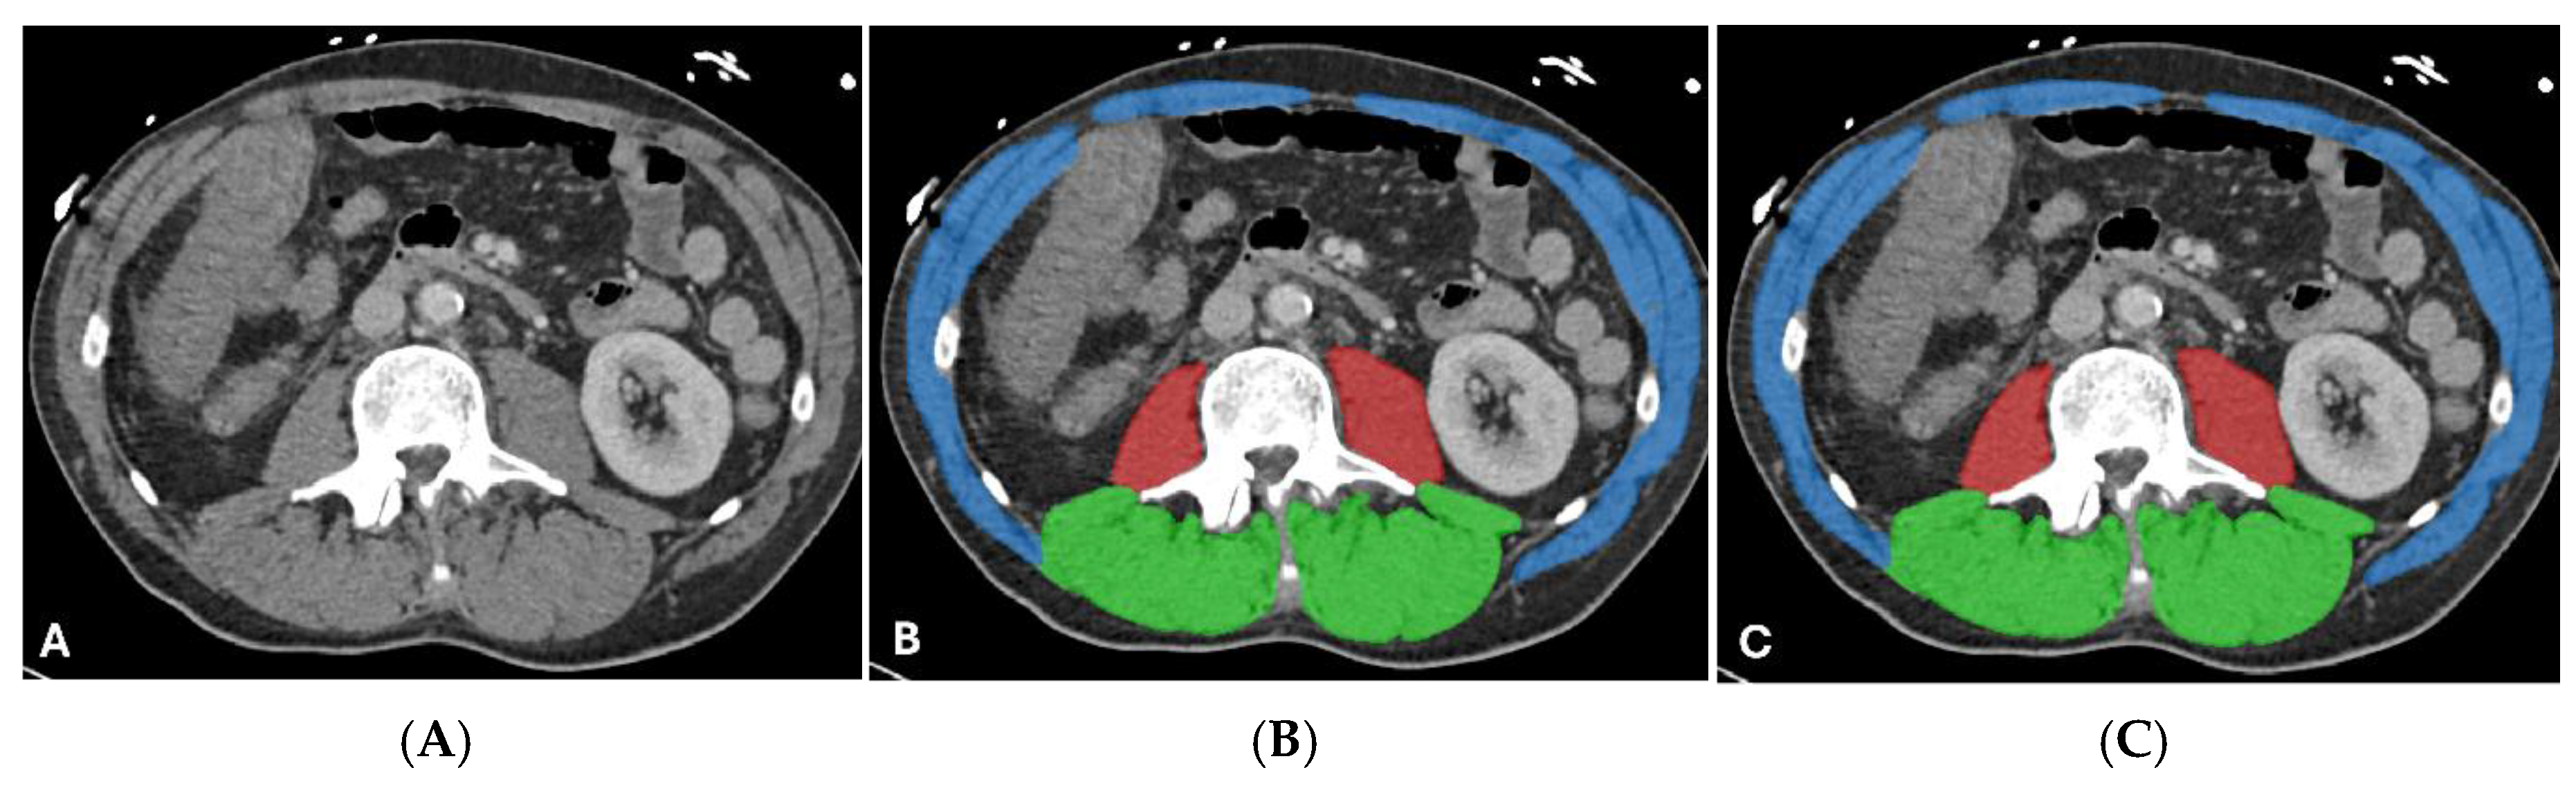

3.5. Qualitative Assessment and Error Analysis